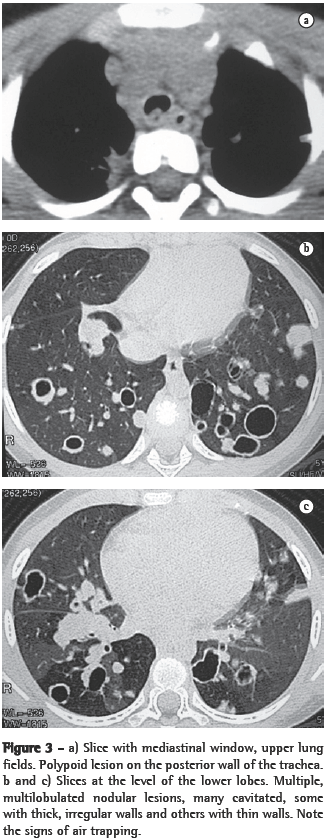

ResultsIn all eight cases, the CT scans revealed polypoid formations in the trachea. In one case, injury to one of the main bronchi was identified. Seven patients presented involvement of the pulmonary parenchyma. In all eight cases, there were cavitated polypoid lesions, with irregular internal borders and walls of various thicknesses, multilobulated in six cases and presenting confluence of the lesions in five (Figures 1 through 5). Solid nodules were seen in six patients. An air-fluid level was observed in only one patient. The lesions were predominantly in the lung bases in three patients and in the middle thirds in two, whereas they were evenly distributed in two. In one patient, the lesions were accompanied by a mass, and, in another patient, they were accompanied by consolidation. In the latter case (Figure 5), there was malignant degeneration in multiple lesions. Signs of air trapping were also observed in one case. There were no identified instances of lymph node enlargement or pleural effusion.

Chest X-rays are inferior to CT scans of the chest, especially those performed using spiral CT (volumetric acquisition), in the initial phases of pulmonary dissemination, due to the fact that CT better characterizes and allows better visualization of nodular tracheobronchial vegetation, Tomographic findings include focal or diffuse airway narrowing caused by the nodules. The nodules form on the mucosal surface, and their invasion into the lumen is best evaluated using CT.(3) These alterations are easily correlated with the disease when there is a clinical history of papillomatosis.(4) Other findings related to airway obstruction and accompanying infections are atelectasis, consolidations, air trapping and bronchiectasis.(2-4) In our sample, polypoid formations in the trachea were observed on all of the CT scans Seven patients presented involvement of the pulmonary parenchyma, characterized by cavitated polypoid lesions with irregular internal borders and walls of various thicknesses, with a multilobulated aspect and a tendency toward confluence. Solid nodules were seen in six patients. None of the patients presented lymph node enlargement or pleural effusion.